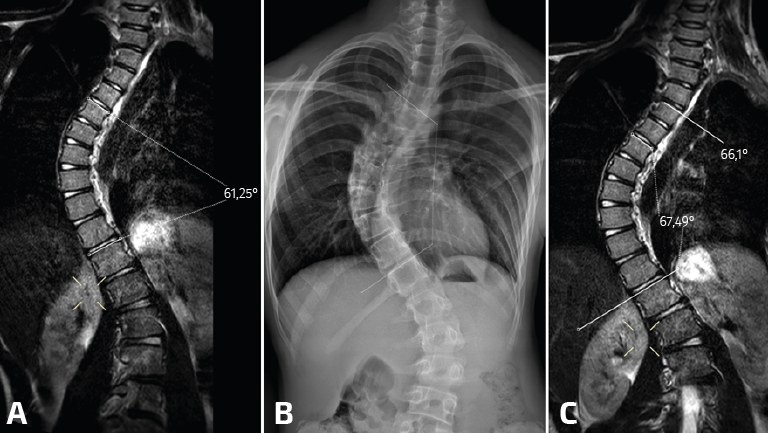

Cualquiera de los sistemas tecnológicos de TC en bipedestación ronda los 300.000 dólares(11). Ello dista de ser asumible por la mayoría de los servicios de traumatología y ortopedia en la actualidad, habida cuenta de que solo se utiliza para el estudio de la articulación del tobillo y el pie. Los estudios de TC en carga axial simulada pueden ser válidos, sin un sobrecoste añadido. Además, estos dispositivos pueden emplearse para el estudio de otras regiones anatómicas. Dado que está fabricado completamente en metacrilato, ha sido utilizado en nuestro hospital para estudios de RM de la cadera o columna con carga simulada (Figura 9)(22).

Figura 9. Resonancia magnética (RM) convencional en supino de columna completa en paciente con escoliosis (A); telerradiografía en bipedestación de columna completa (B); y RM en carga simulada del mismo paciente (C). Nótese el aumento del ángulo Cobb evidenciado en RM con carga simulada que se correlacionó con la radiografía en bipedestación.